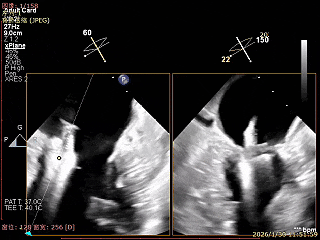

Bicomm切面看2区脱垂

上Color,可见反流主要来自于3区

X-Plane切面切1区未见明显异常

1区上Color,未见反流来源

X-Plane切面切2区可见前叶Flail

2区上Color,可见反流来源

X-Plane切面切3区可见前叶脱垂

3区上Color,可见反流来源